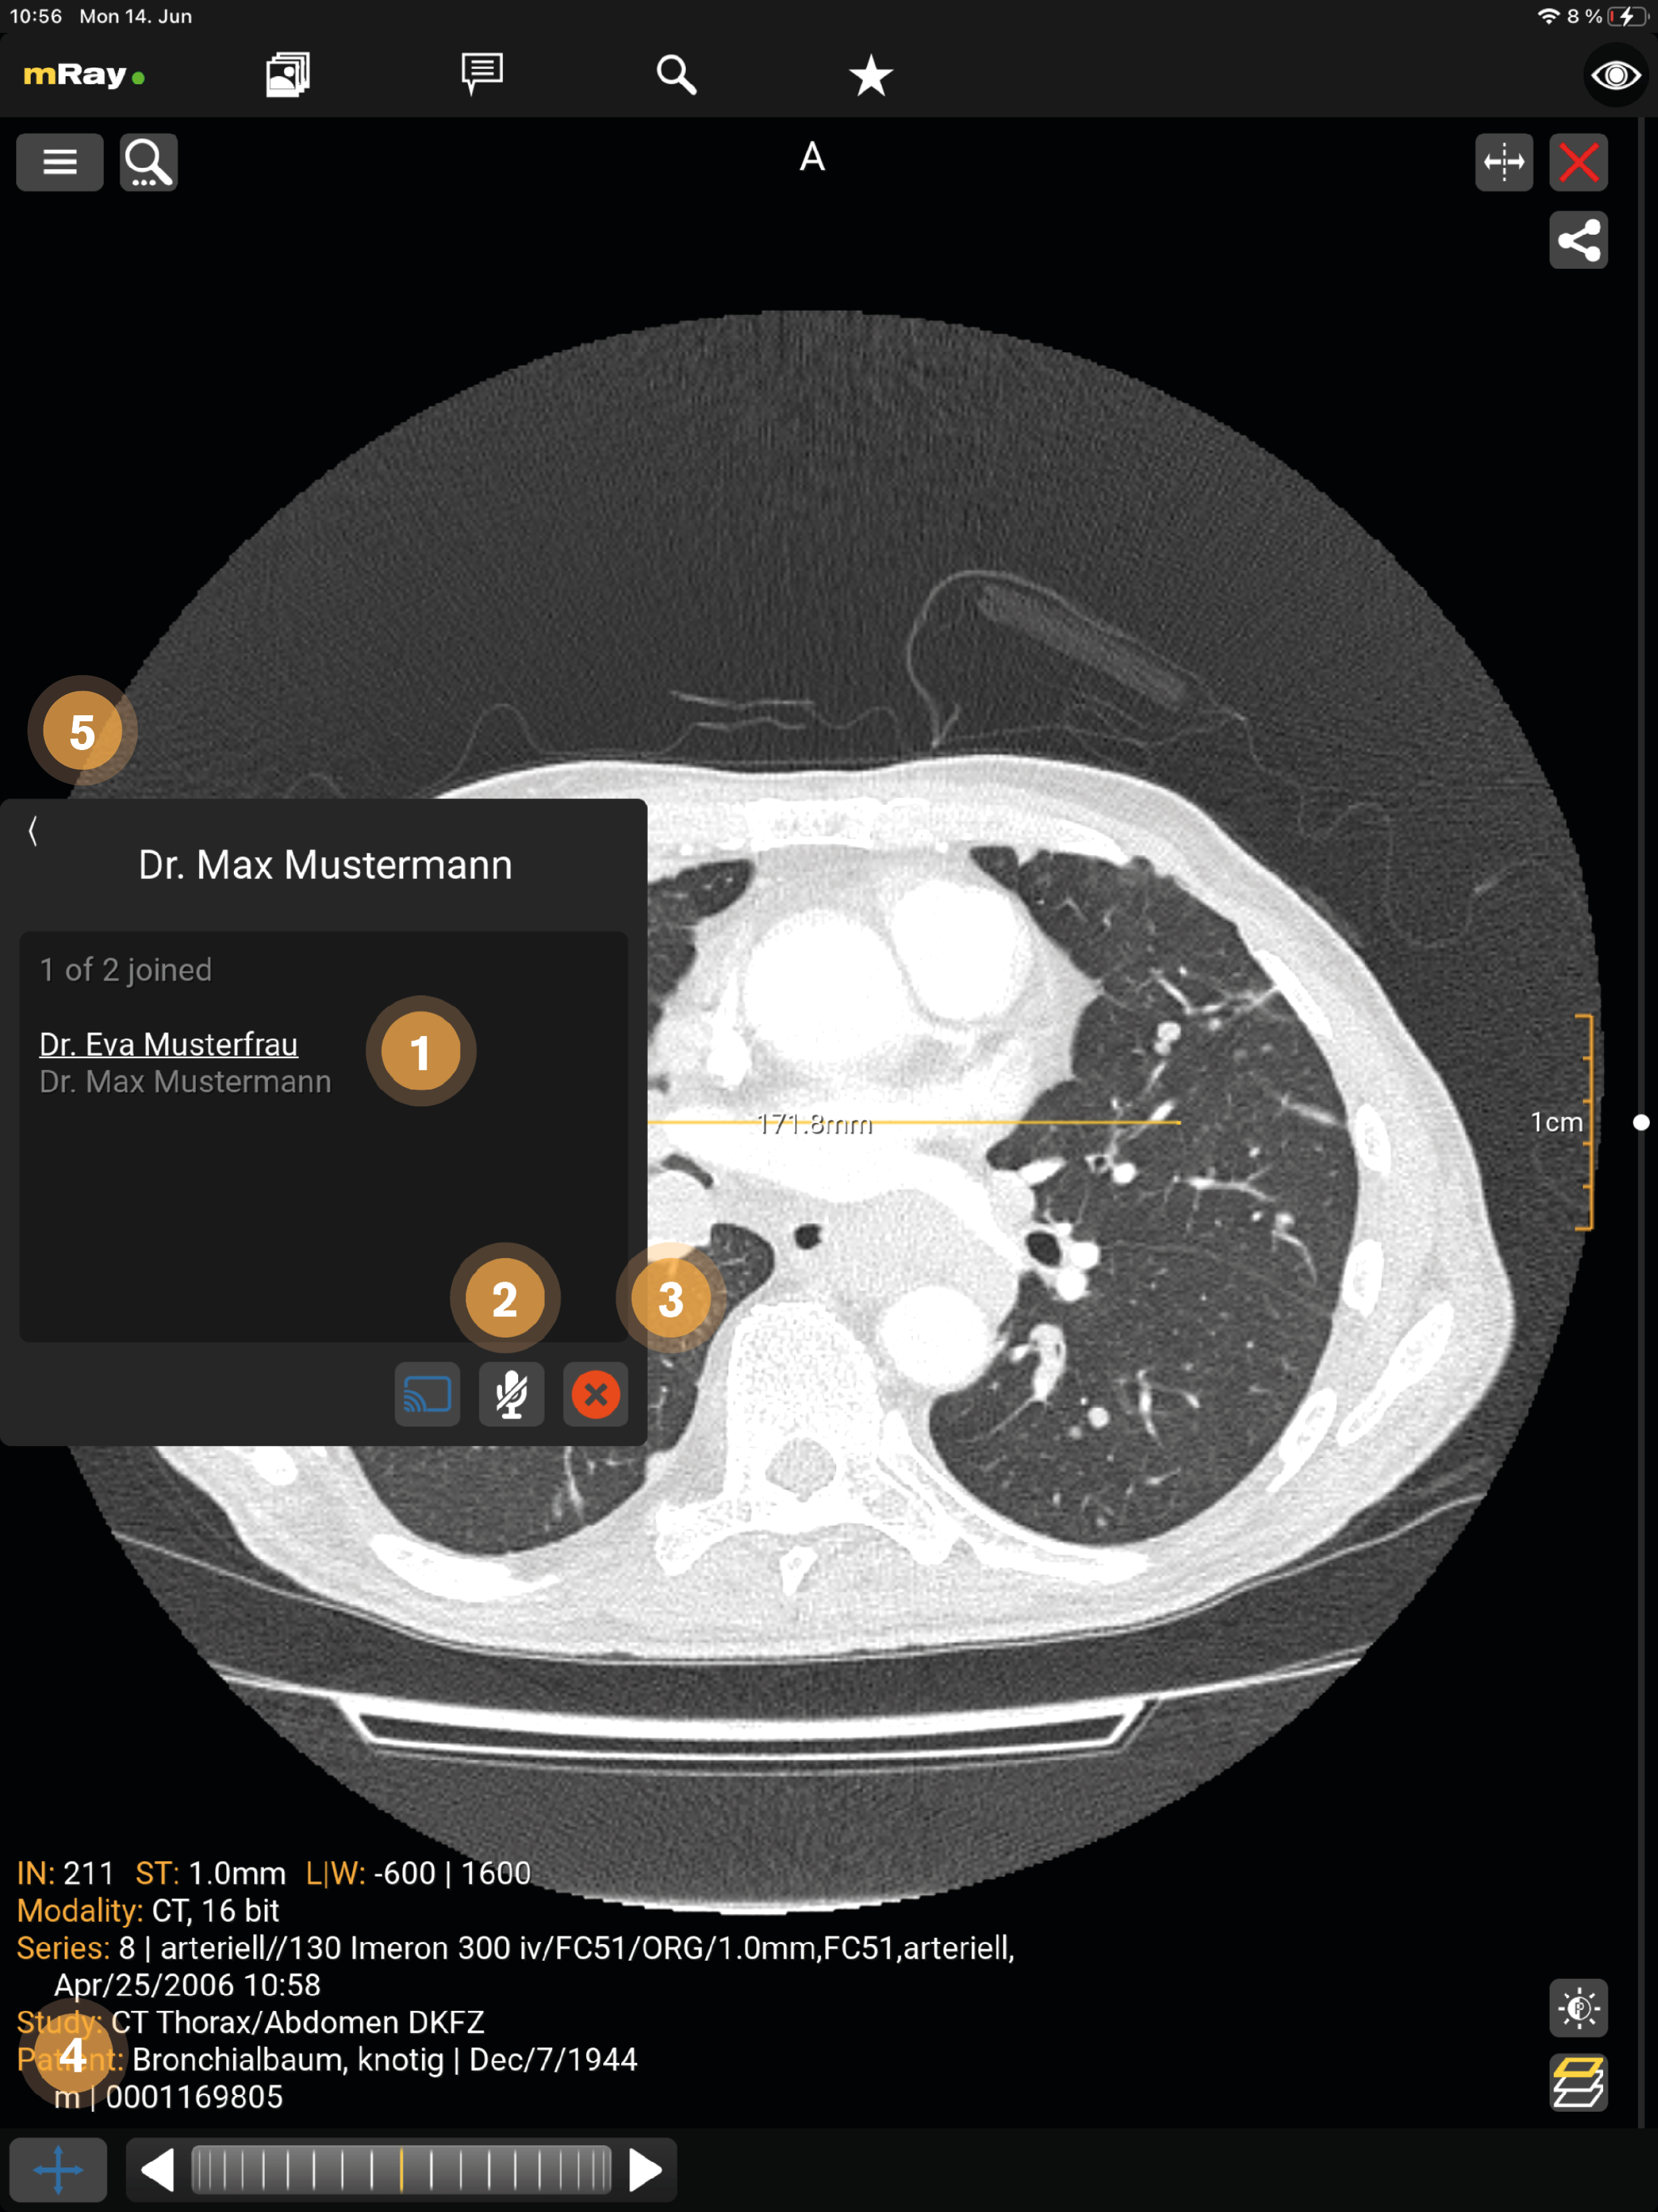

14. Screensharing

Screensharing allows you to share your screen with others. After pressing the button (see Chat) the screensharing will start and the image you have already opened will open (see Chat) or you will be redirected to the inbox if no image has been opened yet. The screensharing can be started with one or more persons (see Screensharing in groups), in the form of a group.

The upper figure visualizes the following functions:

-

The one who started screensharing is underlined in white, the active participants are displayed in white and the inactive participants of the group are displayed in gray.

-

With the 'Microphone' button, a participant can activate and terminate the voice function (crossed out). The speaking participant is displayed in yellow.

-

The X button ends the screensharing for all participants.

-

Only the administrator can apply tools during the screensharing.

-

Here you can minimize the window.

The upper figure visualizes the following functions:

-

By clicking the 'green checkmark' button, the participant can join the screen sharing.

-

The administrator is underlined in white, the active participants are displayed in white and the inactive participants of the group are displayed in gray.